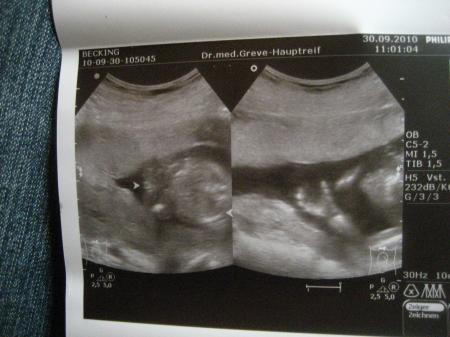

Hier Fotos von heute

Bild zu

Schade man kanns nicht richtig erkennen wei das Foto verkleinert wurde!aber schaut praktisch aus wie ein v das auf dem Kopf steht!